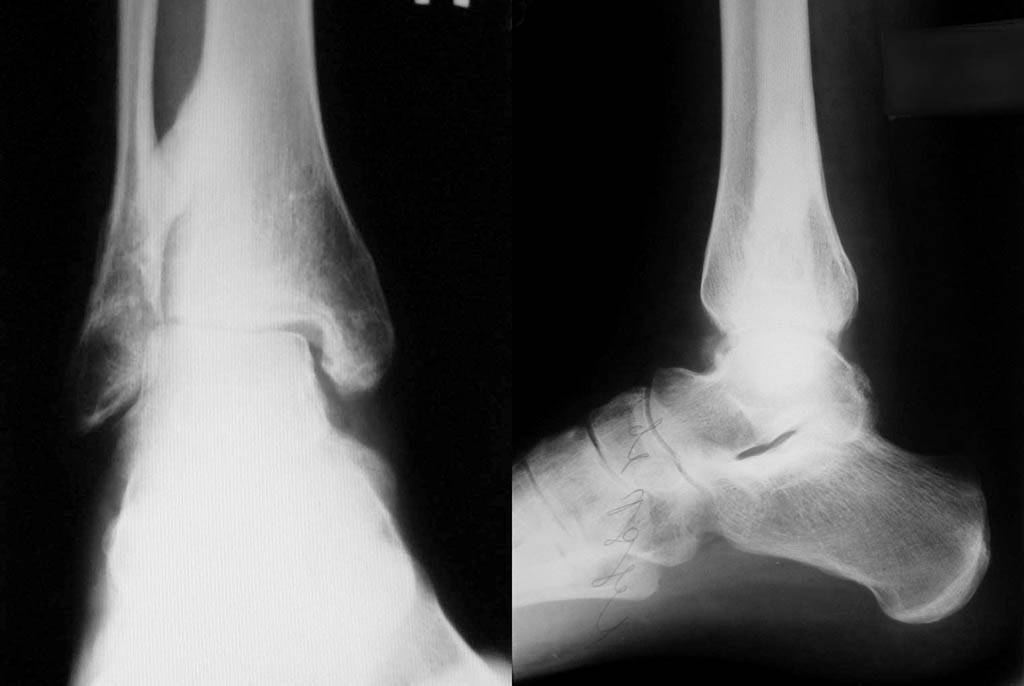

[Ortho] Застарелое повреждение голеностопа

Приложил последние снимки г/стопа.